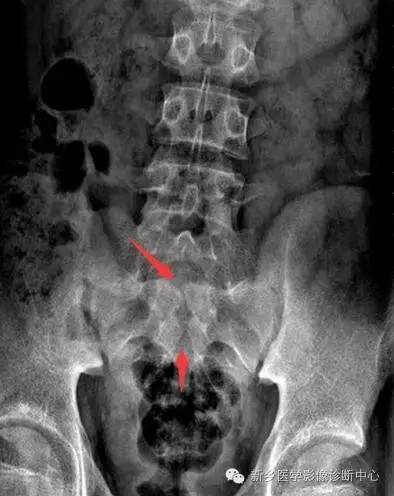

X线:棘突、椎板缺损

(1)隐性脊柱裂:神经管几周围组织已闭合,椎弓存在裂隙,由纤维组织、软骨组织连接,无脊膜或神经组织膨出。